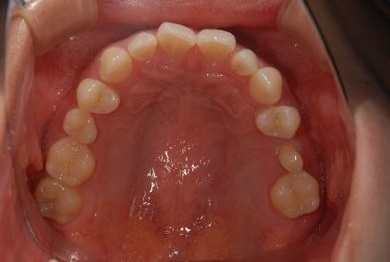

| 主訴 | 下前歯の色が気になるので、ホワイトニングかセラミック治療できれいにしたい。(下前歯2本は乳歯でした) | ||||||||||||||||||||||||||||||||

| 治療方針 | 下顎前歯、乳歯を抜歯し、セラミック治療にて審美的回復を行う。 | ||||||||||||||||||||||||||||||||

| 治療内容 | エンプレスジルコニアフレームオールセラミッククラウンブリッジ4本 | ||||||||||||||||||||||||||||||||